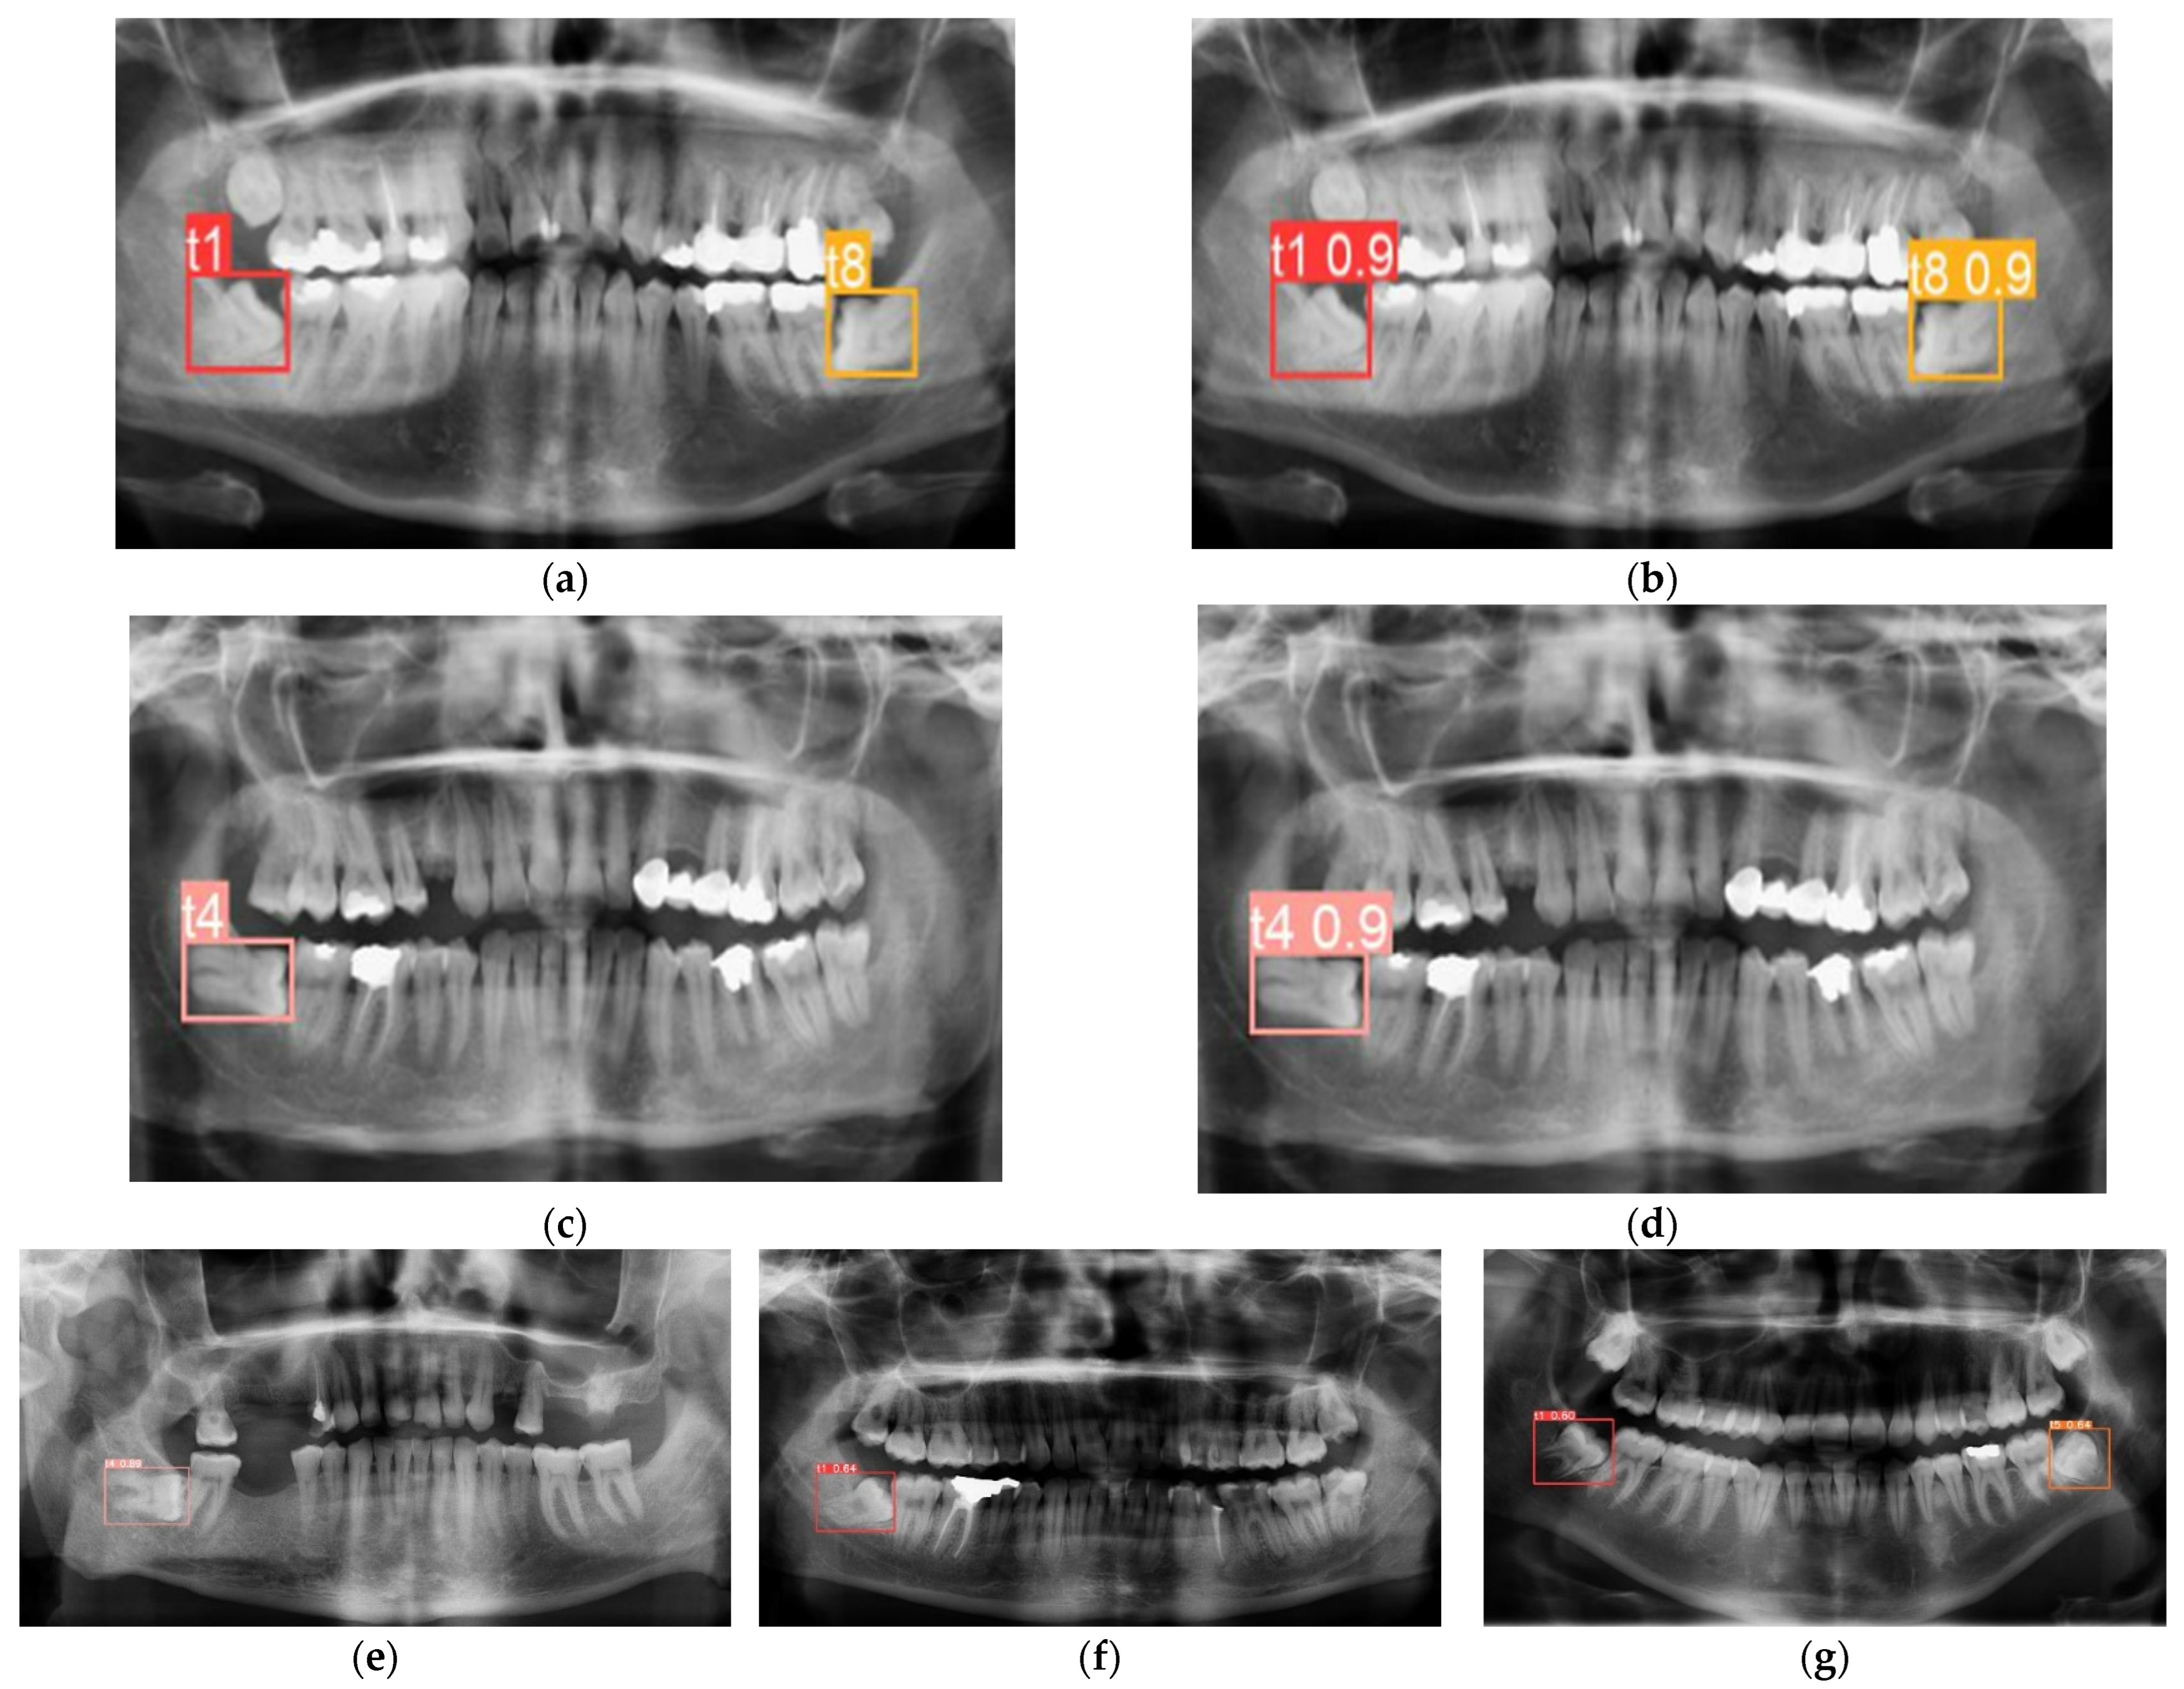

| Class | AP@0.5 | AP@0.5:0.95 | Precision | Recall |

|---|---|---|---|---|

| t1—mesioangular left | 0.96 | 0.774 | 0.849 | 0.95 |

| t4—horizontal left | 0.98 | 0.775 | 0.96 | 0.833 |

| t5—mesioangular right | 0.984 | 0.793 | 0.908 | 0.987 |

| t8—horizontal right | 0.995 | 0.791 | 0.88 | 1 |